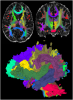

DOTS WM tract segmentation